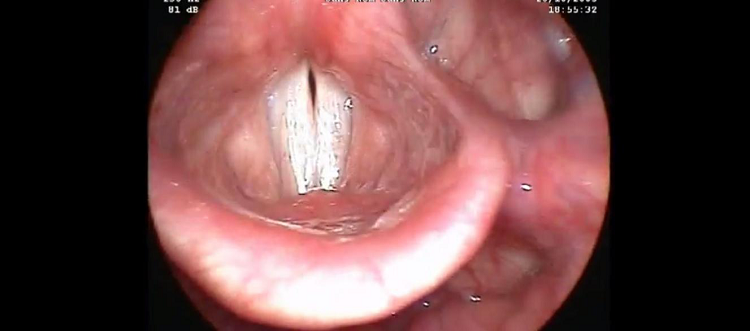

Dans cette étape, l’objective et de renforcer la première étape à travers un FEEDBACH visuel, qui se produira cette fois ci, par la visualisation d’une vidéo de l’examen stroboscopique ou d’une image qui décrit l’état des plis vocaux sur l’écran d’un ordinateur. ( Le bute est d’expliquer au patient la cause physiologique derrière ses problèmes vocaux).

Vidéo de l’examen ORL « stroboscopie » d’un patient qui présente une paralysie récurentielle.

– Par suite, le patient est invité à visualiser une autre vidéo d’une personne qui ne présente aucun problème vocal, en vue de lui motivé à retrouver le fonctionnement phonatoire normale.

Vidéo de l’examen ORL « stroboscopie » de l’affrontement normale des plis vocaux